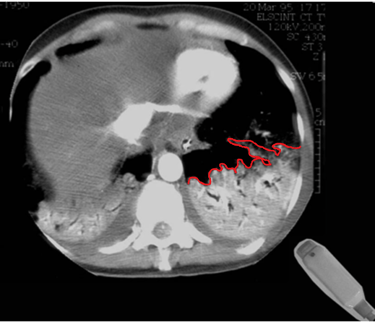

Figura 2. Veja como é possível diagnosticar essa extensa pneumonia utilizando os pontos do protocolo BLUE. Tomografia retirada de https://radiopaedia.org/cases/air-bronchogram-in-pneumonia#image-54184430, e editada pelo autor.

Figura 5b. Consolidação subpleural não-translobar em TC de tórax. Observe a irregularidade da pleura (em vermelho) em contato com o pulmão aerado. Imagem retirada de LICHTENSTEIN, Daniel A. Lung Ultrasound in the Critically Ill: The BLUE Protocol. Cham: Springer, 2016. DOI: 10.1007/978-3-319-15371-1. e editada pelo autor.